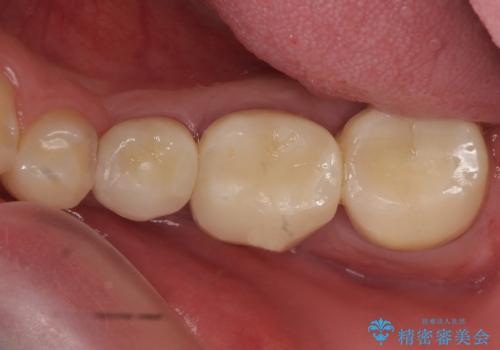

痛みの原因は6番目の虫歯であること、5番目、6番目の歯は歯茎より深い虫歯であり現状では保存が難しいことを説明した上で、歯を挺出させる部分矯正と歯茎を下げる歯周外科を行いました。

手術後歯茎の治癒を待ち、オールセラミッククラウンによる補綴を行いました。

今回用いたオールセラミッククラウンはジルコニアフレームという白い素材の上にセラミックを盛っているため、審美性が非常に高いのが特徴です。

また、ジルコニアは人工ダイヤモンドの材料にも使われているほど高い強度を持っており、そのためオールセラミッククラウンは審美性だけでなく、奥歯やブリッジの補綴も可能とするクラウンです。